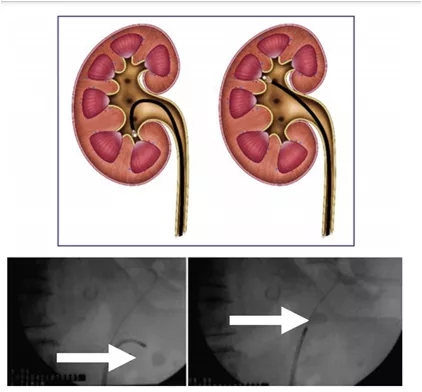

选择最合适的输尿管通路鞘 (UAS) [19]。在进行或不进行输尿管镜检查的情况下放置导丝后,fURS 可能沿着这条安全导丝向上到肾脏或通过第二根导丝(使用双腔插入导管)在透视引导下。另一种选择是将 UAS 置于透视控制下并放入 UAS。UAS 的目标是:促进多个通道用于去除结石碎片,最重要的是提供更好的液体流出冲洗,从而减少肾内压 [2, 20–23]。UAS的选择,它的大小和直径取决于患者的解剖结构,使用的内窥镜和外科医生的偏好 [24, 25]。使用两根导丝,一些新设计的 UAS 仅使用一根导丝,意味着工作导丝变成安全导丝 [26、27](图 1)。必须注意UAS 放置期间施加的力,因为输尿管损伤可能是强制操作的结果。此外,在第二次治疗过程中,可能会出现结石碎片,这些碎片可能已经迁移到输尿管,必须在任何 UAS 插入之前移除。如果有的话, UAS 放置过程中会遇到阻力,后者应停止并引入内窥镜探查输尿管。如果不可能,放置输尿管支架更安全,可以用于输尿管被动扩张,使以后的二次 fURS 手术更容易执行。UAS 的最佳位置是其尖端在输尿管近端或只是在输尿管肾盂交界处下方但不越过它,因为这是输尿管撕脱风险最大的部分,因为这里肌肉组织支持最少。把这些考虑到数据,建议根据 fURS 轴的尺寸配件使用尽可能小的 UAS。根据使用的 fURS,我们建议使用 10/12-Fr UAS 作为一线选择,因为对肾内压和冲洗条件来说, 它是最好的折衷方案

图 1 输尿管通路鞘。内尖端的移除自动将工作导丝作为安全导丝横向转换为护套